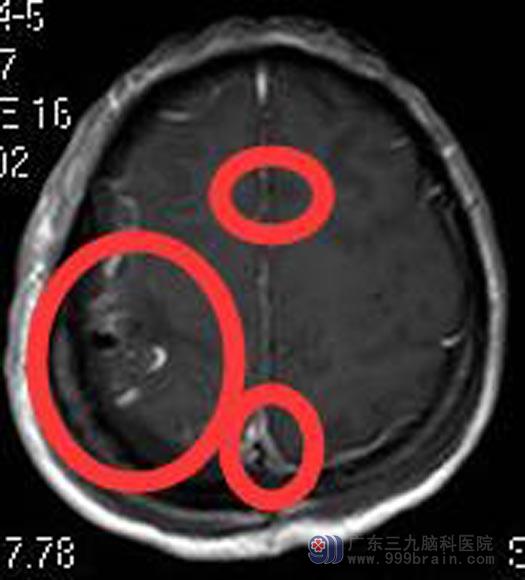

三个肿瘤都准确无误地彻底切除,术后张女士恢复良好,肢体活动正常,没有遗留后遗症。术后病理示:1、(右侧顶部)非典型脑膜瘤,WHO II级;2、(大脑镰)脑膜瘤组织;3、(大脑镰)脑膜瘤组织。

手术后